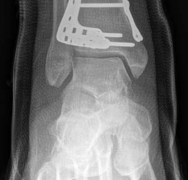

Articular Reconstruction

The first objective of the internal fixation phase is the anatomic reconstruction of the articular block. The joint capsule is incised to allow direct visualization of the plafond. A femoral distractor or a temporary external fixator spanning the joint can be utilized to gain joint space and visualize the central impacted fragments. Using a dental pick or a Freer elevator, the central die-punch fragments are carefully disimpacted and brought down flush with the talar dome.

Image

Once the articular surface is visually and fluoroscopically reduced, the resultant metaphyseal void is densely packed with cancellous allograft, autograft, or synthetic bone substitute to prevent late subsidence. The major articular fragments (Chaput, Volkmann, and medial malleolus) are then reduced around the central reconstructed block using pointed reduction forceps. Provisional fixation is achieved with multiple 1.6mm or 2.0mm Kirschner wires. Independent 3.5mm or 4.0mm lag screws can be placed outside the planned footprint of the definitive plate to secure the articular block.

Metaphyseal-Diaphyseal Fixation

With the articular surface reconstituted, the surgeon's focus shifts to bridging the complex metaphyseal-diaphyseal dissociation. A pre-contoured anatomical locking plate is slid submuscularly or subcutaneously along the diaphysis using a MIPPO technique. The plate is positioned on the anterolateral or medial surface, depending on the preoperative plan and soft tissue constraints.

The distal portion of the plate is secured to the reconstructed articular block. It is imperative that the distal locking screws are placed parallel to the joint space, forming a rigid subchondral raft that supports the articular cartilage. Fluoroscopy is utilized extensively to ensure no screws have penetrated the joint. Once the distal block is secured to the plate, the diaphyseal segment is aligned. Length, alignment, and rotation are restored using manual traction or the femoral distractor. The proximal portion of the plate is then secured to the diaphysis using a combination of non-locking screws (to pull the bone to the plate) and locking screws (to create a fixed-angle construct). The working length of the plate is maximized by leaving several screw holes empty over the zone of comminution, promoting secondary bone healing.